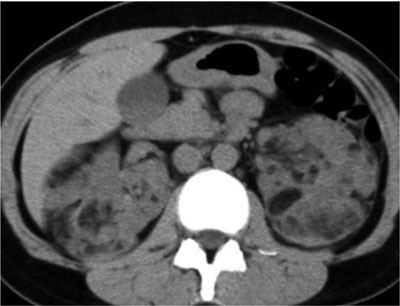

Figure 2

UECT showing bilateral and multiple AMLs in a patient with TSC. Each lesion contains attenuation numbers less than –10 HU, consistent with fat-rich AML [3].